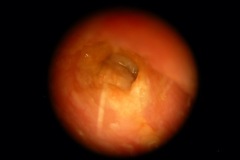

Ear Canal

Wax